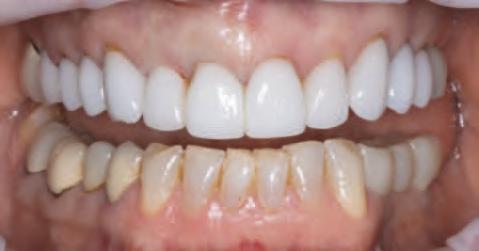

Rezultatele recenziei

În zonele edentate cu d sponb l tate osoasă comprom să în d mens un le vert cale sau or zontale, mplantur le scurte ș /sau cu d ametru îngust sunt modal tăț alternat ve de tratament la procedur le de grefare osoasă pentru plasarea convenț onală (f g. 1, 2). Implantur le scurte (lung mea <10 mm) pot f plasate fără grefare osoasă vert cală. În general, lățmea mplantulu este cons derată ma mportantă decât lung mea acestu a pentru d s parea stresulu . Zona osulu crestal pr mește pres unea max mă, ar spre porț unea ap cală a mplantulu se

Figurile:

1. Utilizarea implanturilor scurte (lungime 6 mm) pentru a evita o augmentare cu grefă de sinus.

2. Utilizarea mai multor implanturi de dimensiuni mici, de tip monobloc, pentru a restaura o arcadă maxilară edentată îngustă fără grefare.